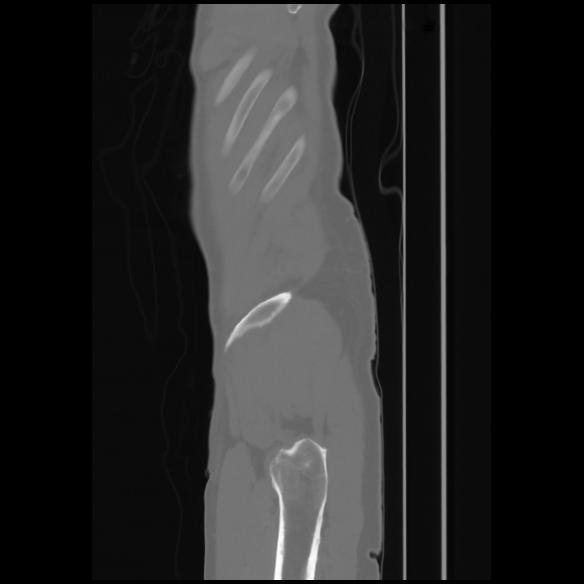

7 CUERPO,CE,Sagittal,3.000,CUERPO,Sagittal,